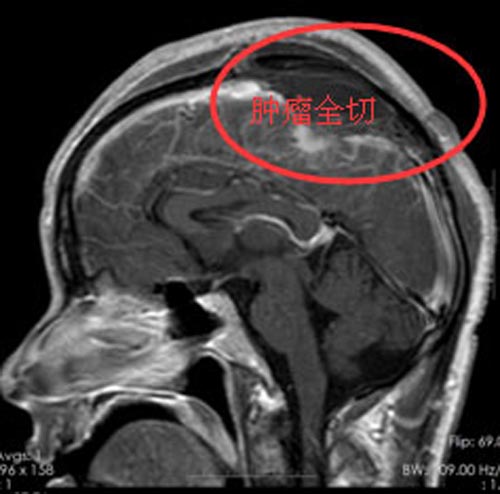

完善术前准备后,外五科医生团队在全麻下为文先生行“左侧顶部大脑镰窦脑膜瘤切除术+上矢状窦重建术”,术中采用导航定位,剪开硬脑膜,肿瘤与硬膜粘连,质中偏硬,血运丰富,广基与大脑镰相连,大小约4.0cm×5.5cm×3.5cm,完全切除肿瘤,手术顺利,未予输血,术后给予脱水、改善微循环等对症治疗。

术后第二天,文先生即神志清醒,查体合作,语言清晰,问答切题,视力及视野未见异常,未再出现肢体抽搐情况,恢复良好。